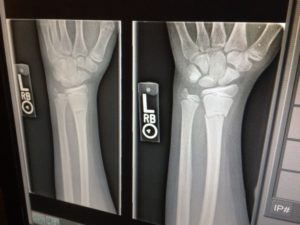

Røntgenundersøgelse

08 februar 2024